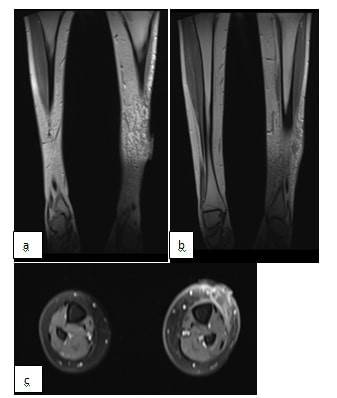

Sellülit, derin dermis ve deri altı yağ dokusunu içeren derinin akut bir enfeksiyonudur. Klinik belirtiler; kızarıklık, şişlik, sıcaklık ve hassasiyet gibi enfeksiyonun görüldüğü bölgede ortaya çıkar. Sellülit tedavi edilmezse ciddi komplikasyonlar, nekroz, apse ve osteomiyelite yol açabilir. Streptococcus pyogenes ve Staphylococcus aureus (S. Aureus) en sık izole edilen bakteriler arasındadır. Bu bakteriler genellikle deri bütünlüğünün bozulduğu yerlerden dokuya ulaşmaktadır. Hastalarda nadir durumlarda selülit çevre dokulara yayılabilir, apse oluşumunu veya osteomiyeliti tetikleyebilir. Bu yazımızda travmaya sekonder sol tibia ön yüzde selülit olarak başlayan, giderek ilerleyerek apse ve çevre dokuda nekroz gelişimine sebep olan sellülit-apse vakası sunulmuştur. Bilinen hastalığı olmayan 17 yaşında erkek hasta, 10 gün önce merdivenden düşme sonrası sol bacak ön yüzde başlayan şişlik ve kızarıklık şikayeti ile başvurdu ve sellülit tanısı aldı. İzlemde nekrotik yumuşak doku enfeksiyonu gelişti ve yara kültüründe S. aureus üremesi oldu. Olgumuz komplikasyonsuz şekilde başarıyla tedavi edildi. Cilt ve yumuşak doku enfeksiyonlarını tedavi etmek için genellikle birinci kuşak sefalosporinler ve antistafilokokal penisilinler ilk tercihlerdir. Ancak, metisilin dirençli S. aureus (MRSA) tarafından oluşturulan enfeksiyonları etkin bir şekilde kontrol etmeyebilirler. Antibiyotik seçimi önemli olsa da, enfekte yabancı cisimlerin çıkarılması, apse varsa cerrahi olarak drenajı ve düzenli yara temizliğinin sağlanması gibi destekleyici önlemler başarılı bir iyileşme için hayati öneme sahiptir. Sonuç olarak, cilt ve yumuşak doku enfeksiyonlarını yönetmede klinik değerlendirme çok önemlidir. Çünkü laboratuvar sonuçları hastanın durumunu tam olarak yansıtmayabilir. Ampirik antibiyotik tedavisi; lezyonun şiddeti, klinik durum ve muhtemel patojenler göz önünde bulundurularak derhal başlatılmalıdır. Etkilenen bölgeden kültür almak, etkeni tanımlamada ve antibiyotik direnç

paternlerini belirlemede yardımcı olur ve buna göre tedavi planını yönlendirir.